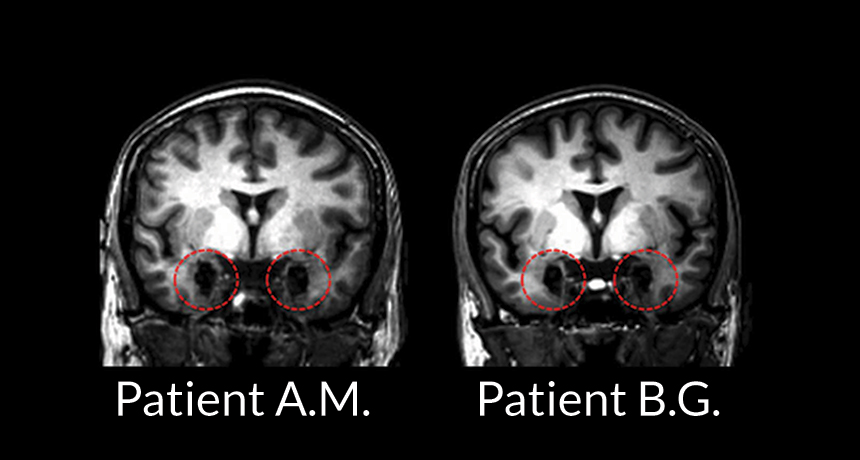

FEAR FACTORS Despite extensive damage in their amygdalae (red circles in these MRI scans), twin sisters A.M. and B.G. still can experience anxiety prompted by bodily cues, a new study shows.

S. Khalsa et al/Journal of Neuroscience 2016